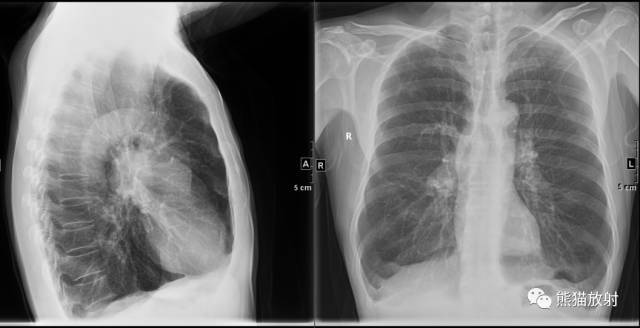

肺气肿x线胸片图解

肺气肿x线胸片图解,

胸片上小叶中心型肺气肿常表现为上叶显著的肺透光度增高,肺纹理减少

肺气肿胸片影像

肺气肿的胸片表现